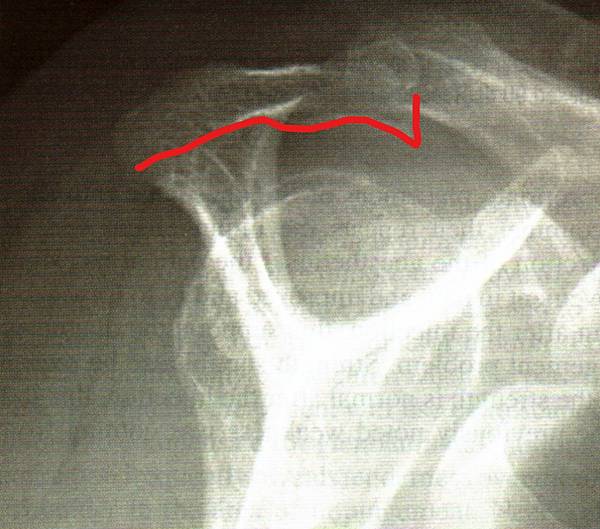

棘上肌出口像(supraspinatus outletviews)可看肩峰的骨性結構外形(morphology)

正常的肩峰結構:平滑的肩峰下曲線

異常的肩峰下結構可見一往下延伸的骨刺